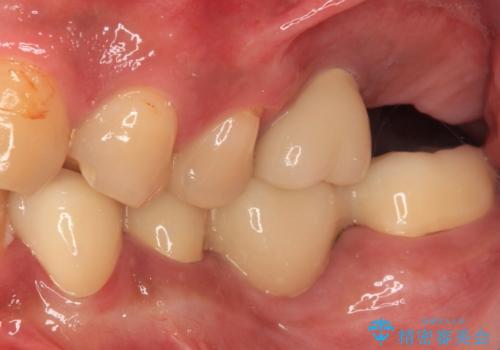

目立つ金属をすべてセラミックに 全顎的メタルフリー治療

しかしながら、左下の抜歯部位は骨欠損が著しく大きく、多大な垂直的骨造成を要するため、3歯を支台としたブリッジによる補綴治療とし、右下のみをインプラント補綴としました。

小さい修復物の銀歯が装着されている歯はセラミックインレーにて、その他はオールセラミッククラウンにて補綴治療を進めることとしました。

矯正治療にも最初は興味を持たれていましたが、抜歯矯正の可能性が高いことや、治療期間、後戻り防止のためのマウスピース使用などが煩わしいと感じ、補綴治療のみを行うこととなりました。